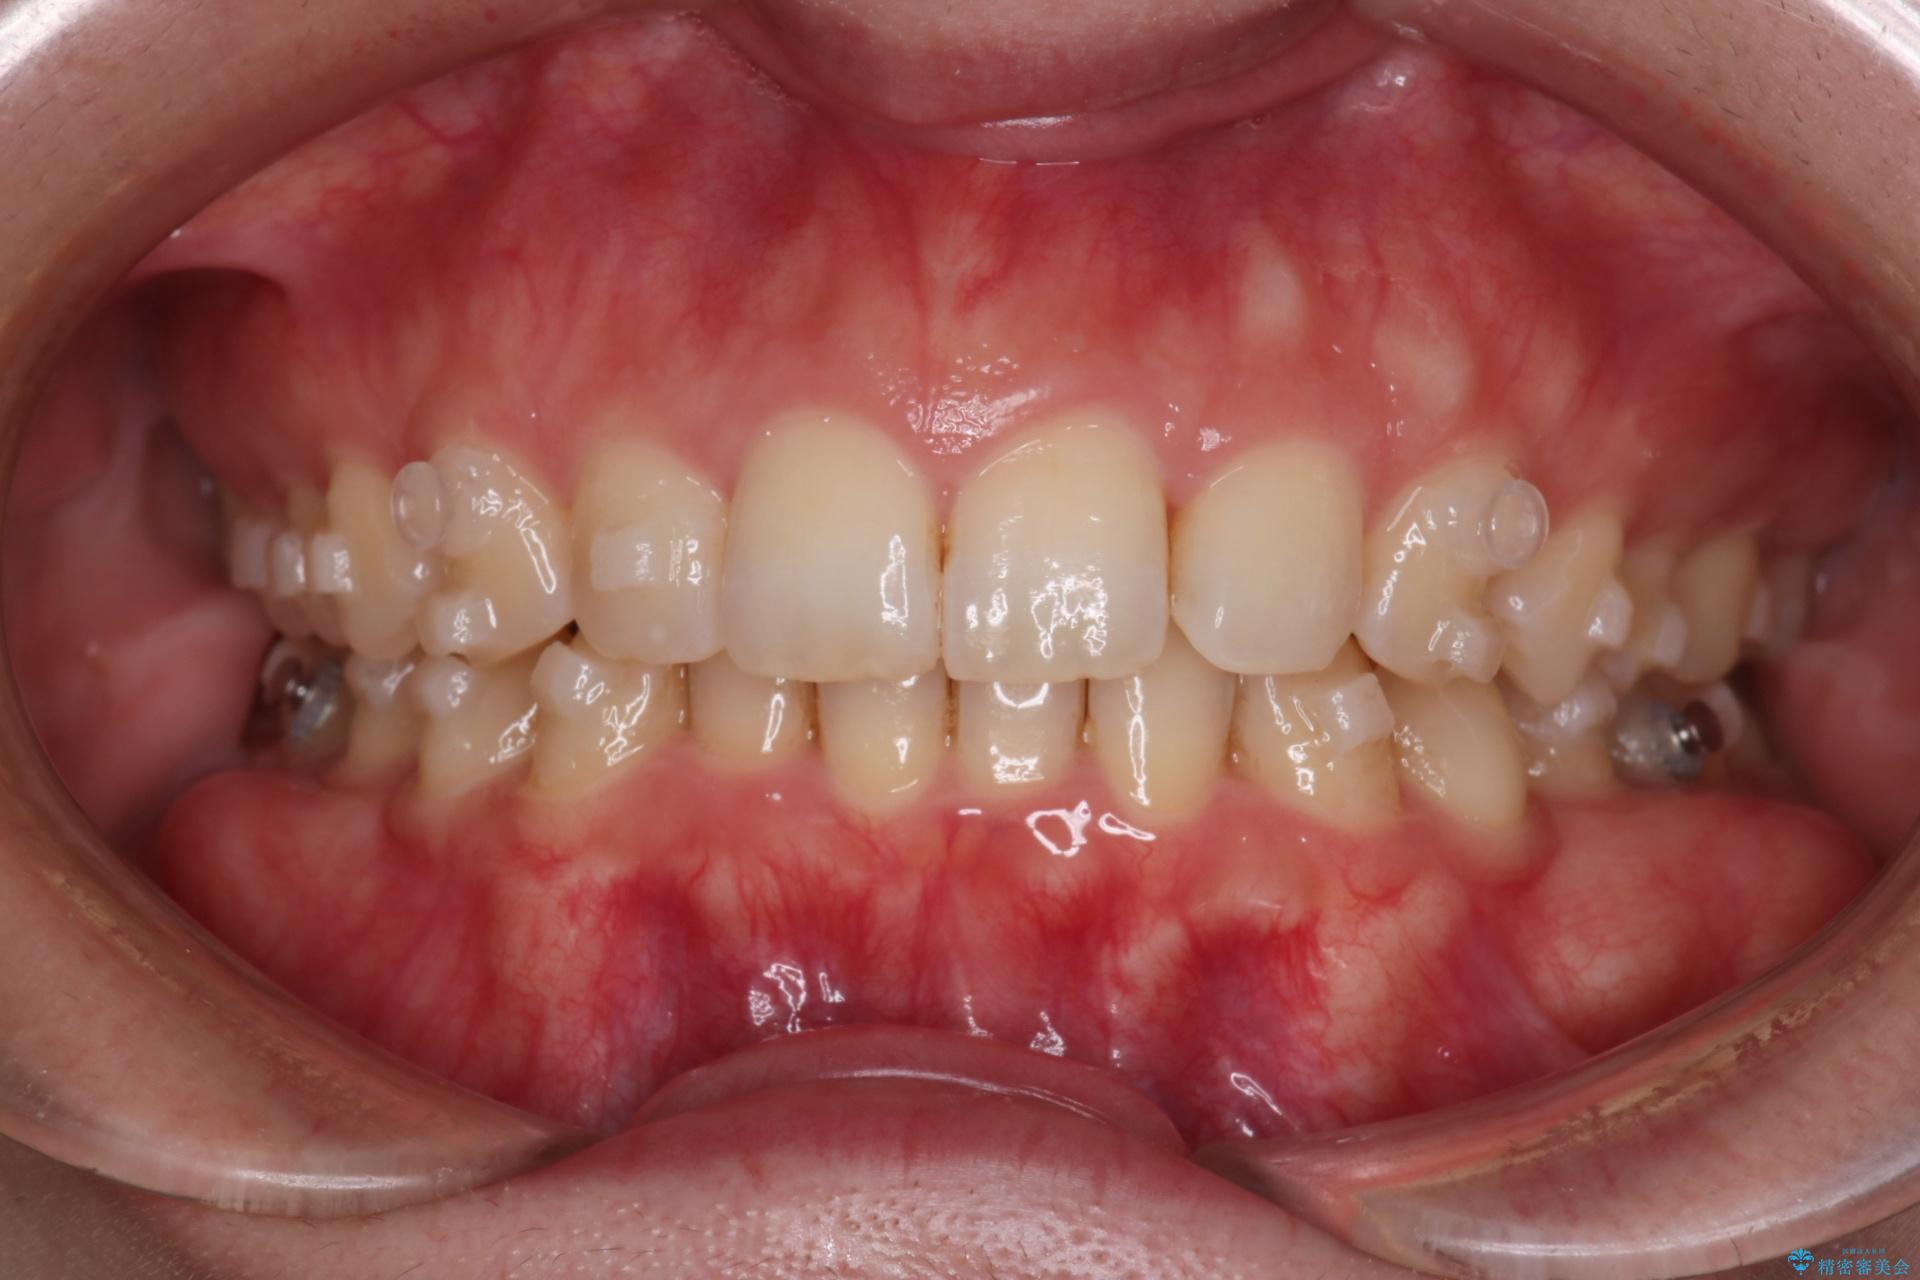

噛み合わせをよくするために、ワイヤー矯正とインビザライン矯正のどちらの期間も必要な箇所にゴム掛けを行いながら治療を行いました。

ゴム掛けを頑張っていただいたので、噛みあわせも改善され綺麗な歯並びになりました。